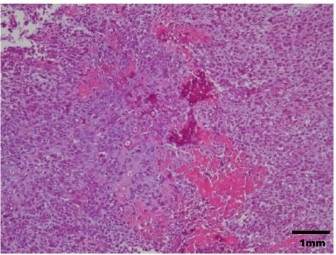

A 14-year-old spayed female Labrador retriever weighing 21.3 kg was referred to our hospital with a main complaint of chronic right-hind lameness. This patient had undergone surgery for right tibial fracture repair with implantation of bone plate and screws at a referral hospital 12 years ago. The patient showed no appetite, was not drinking, and was lethargic, with a body condition score of 1/5. The patient was unable to stand up on her own, her right hind limb was mostly weak, and she was unable to move independently using her left side. The patient’s state of consciousness was normal. On physical examination, her vital signs were normal (temperature: 38.1°C, pulse 104 beats/minutes with no heart murmur, respiratory rate with normal lung sounds: 32 beats/minutes). The mucous membrane showed a pale color because of severe anemia (packed cell volume 20.4%). In addition, the capillary refill time was delayed by <3 seconds, suggesting severe dehydration. The patient showed swelling and was warm to the touch from the right tibia to the femur, with a swollen right popliteal lymph node, which presented with a ruptured mass lesion approximately 7 × 10 cm in size. The thoracic radiograph was normal (Fig. 1). However, the right hind limb radiograph showed an osteolytic lesion accompanying the ruptured implant and loosening of the plate and screws, with surrounding soft tissue swelling (Fig. 2). Fine needle aspiration from this site suggested OSA (data not shown). Although we could not perform angiographic computed tomography because of the owner’s dissent, we performed amputation from the hip joint on the same day. Gross morphology showed severe inflammation surrounding soft tissues, the rupture of the stainless-steel bone plate, and we noted a non-medical band at the right tibia (Fig. 3). The patient was formally diagnosed with OSA after histopathological examinations (Fig. 4). After 24 hours hospitalization, we administered ampicillin potassium (20 mg/kg, BID) intravenously and prednisolone (0.5 mg/kg, SID) subcutaneously for postoperative care. Also, 24 hours continuous rate infusion of fentanyl (5 μg/kg/minutes) in lactated Ringer’s solution was used for analgesia. The patient was discharged to the owner the day after surgery for home care. The owner refused postoperative radiation therapy and chemotherapy. Unfortunately, this patient died 1 month after amputation.

Fig. 4. Histopathological diagnosis was OSA.